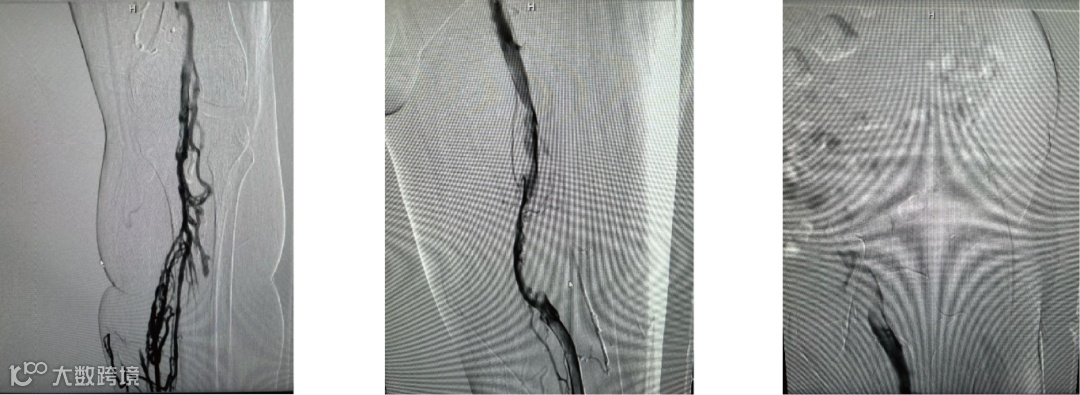

患者全程取俯卧位,左下肢常规消毒铺单,B超引导下穿刺左腘静脉,导入10F短鞘,经血管鞘造影,证实左腘股髂静脉血栓形成。鳅导丝配合单弯导管通过闭塞股静脉,造影证实导管位于下腔静脉。

导入10F天航外周血栓抽吸导管+天戟分离器于大腔导管行机械血栓清除

导入(10*60mm)球囊行髂静脉扩张

导入支架(14*100mm,)覆盖髂静脉狭窄处,再次造影见狭窄消失,股静脉回流通畅,原滤器内未见明显血栓形成,无造影剂外溢。拔管,穿刺点压迫止血,加压包扎。麻醉满意,术后患者安返病房。

最后造影见支架内血流通畅,侧枝消失

造影可见:髂静脉 和股静脉血流复通